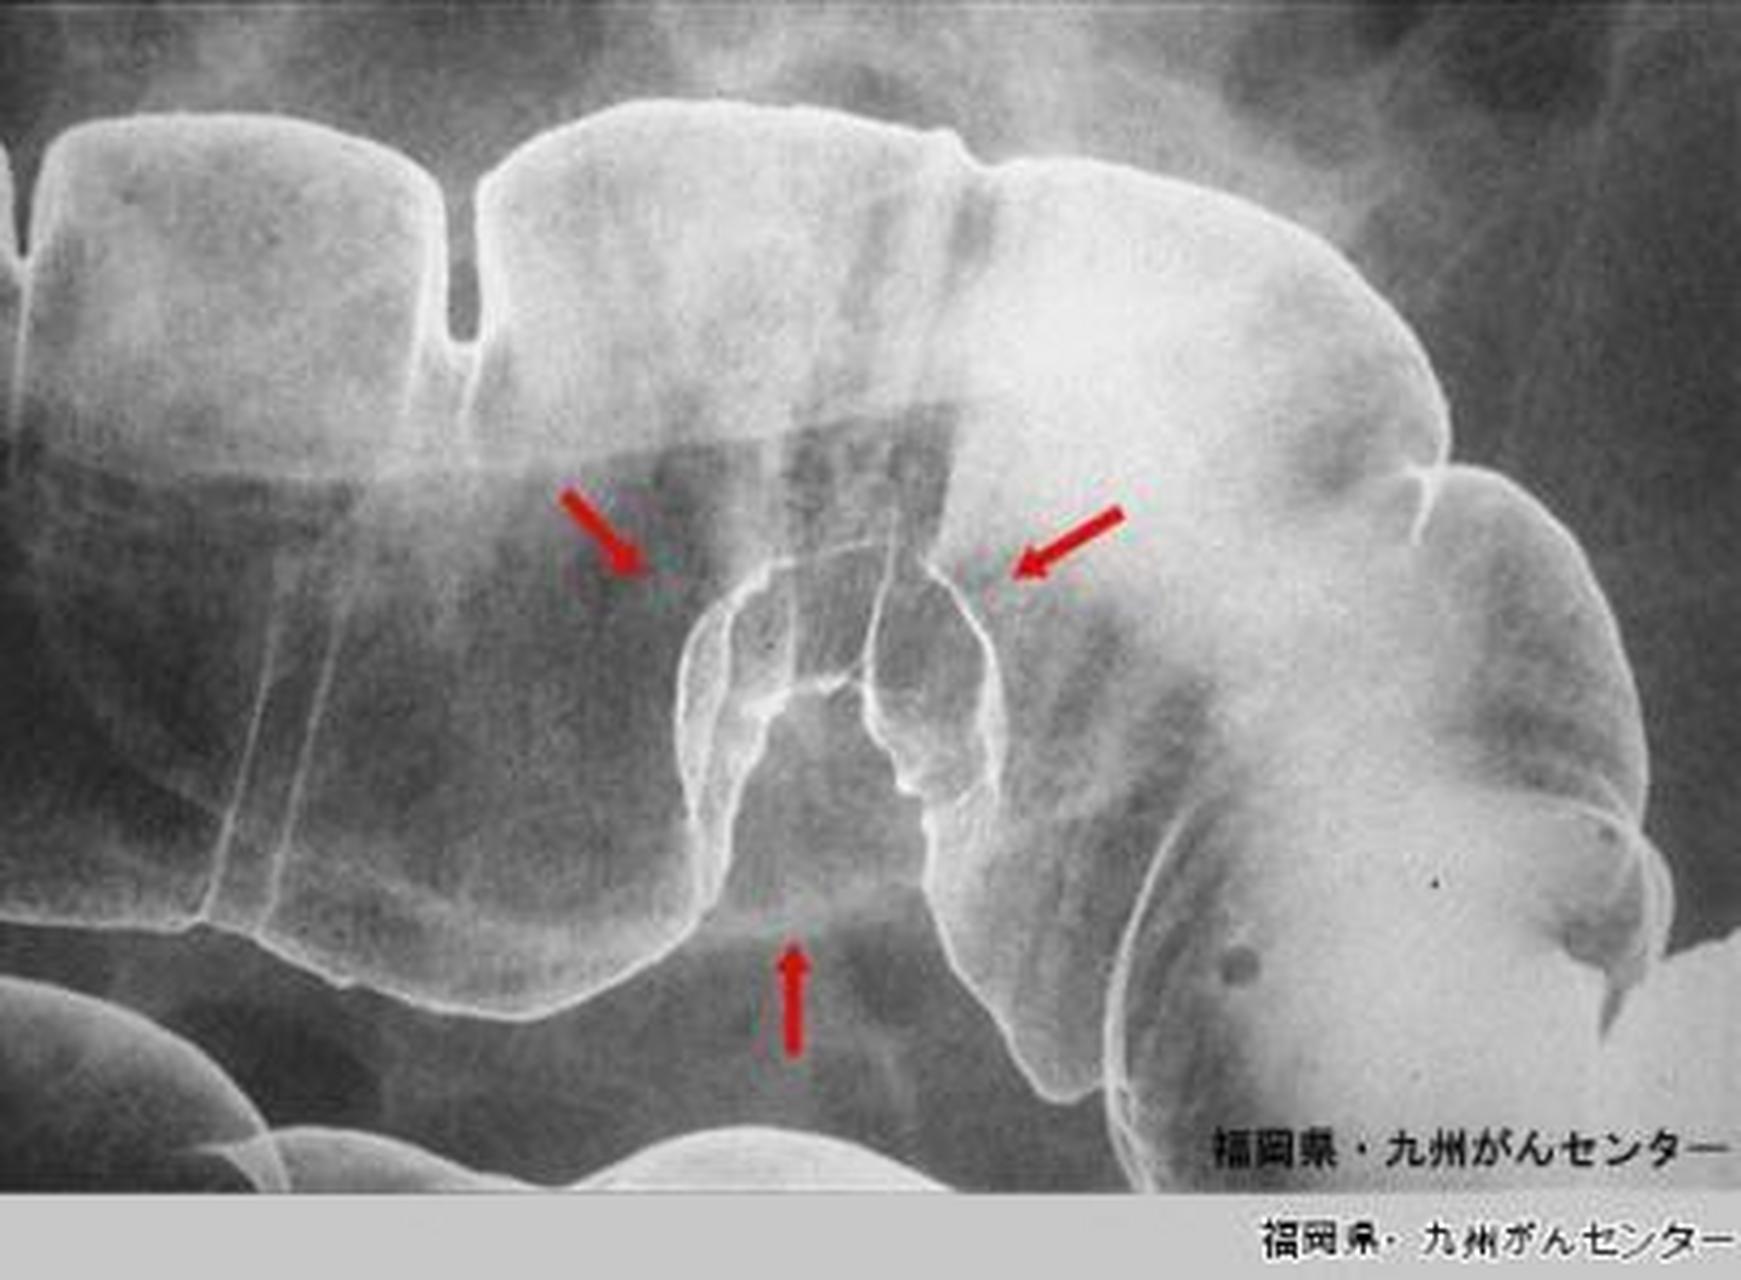

钡餐造影和胃镜的区别